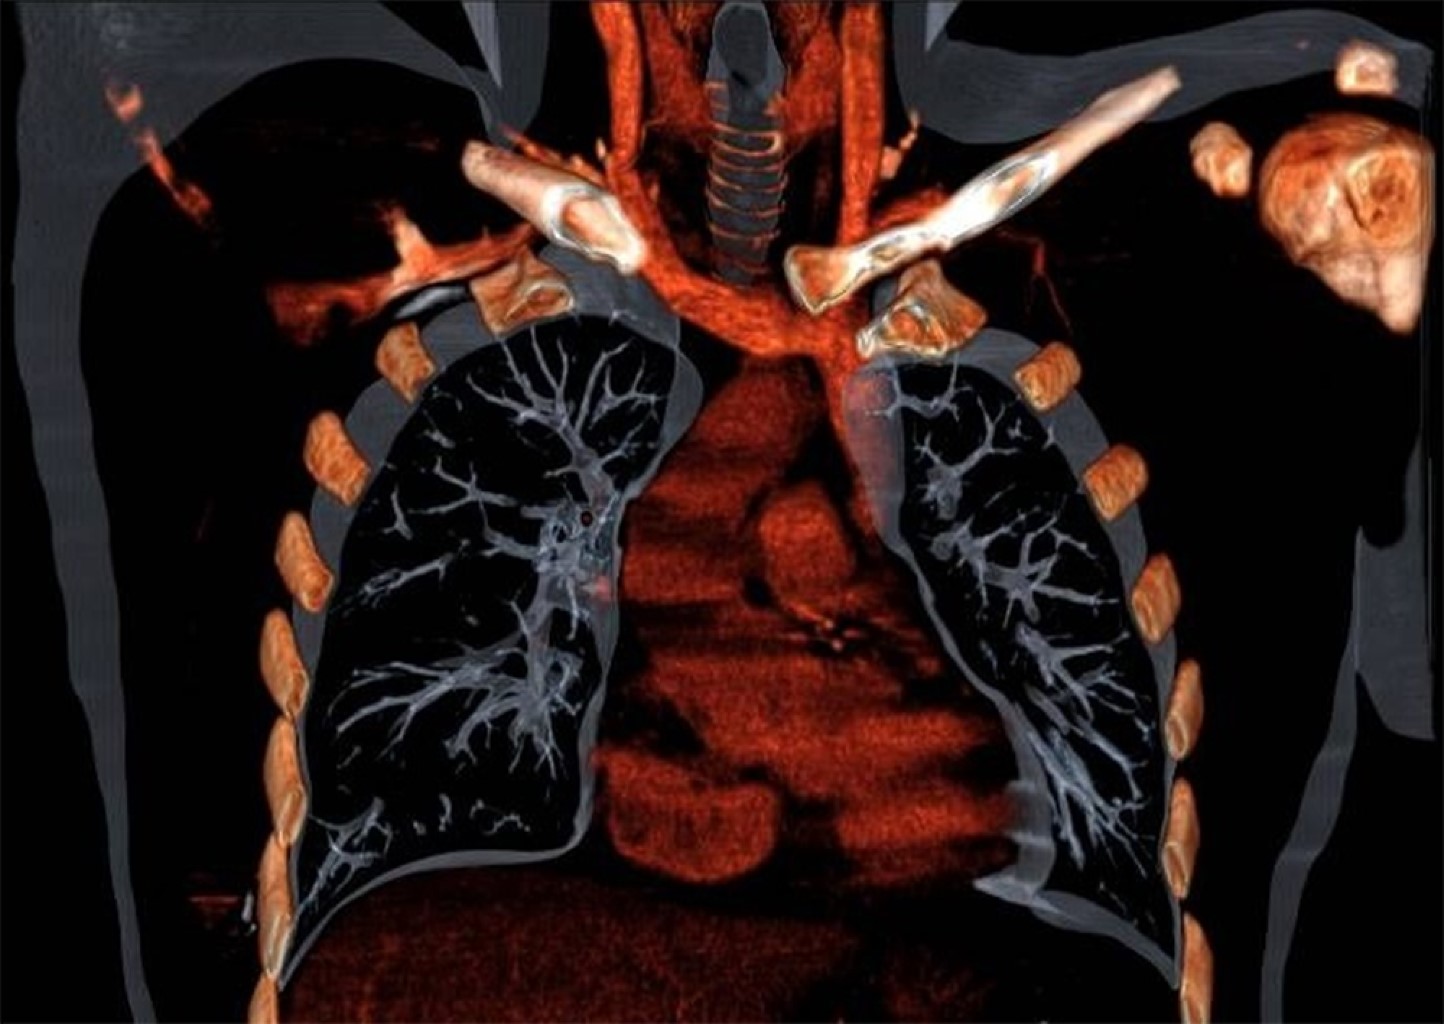

Malposition of central venous catheters is associated with important and underestimated risks. Although some factors have been related with malposition, its cause is generally not diagnosed, and it seems to have multifactorial origin. We present two cases of central venous catheter malposition due to unusual anatomical causes, diagnosed in the perioperative period. In the first case, superior vena cava agenesis was diagnosed during mitral replacement by sternotomy, which was logically associated with malposition of the inserted central line. The use of catheters and devices through jugular and subclavian veins in patients with this infrequent pathology is associated with important limitations and serious potential complications. In the second case, an undiagnosed goiter causes bilateral and simultaneous malpositioning of two inserted central venous catheters, in the context of an emergency situation, in both internal jugular veins.

Figure 3